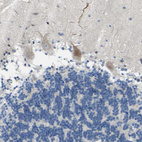

Immunohistochemical staining of human cerebral cortex shows moderate cytoplasm granular positivity in neuronal cells.